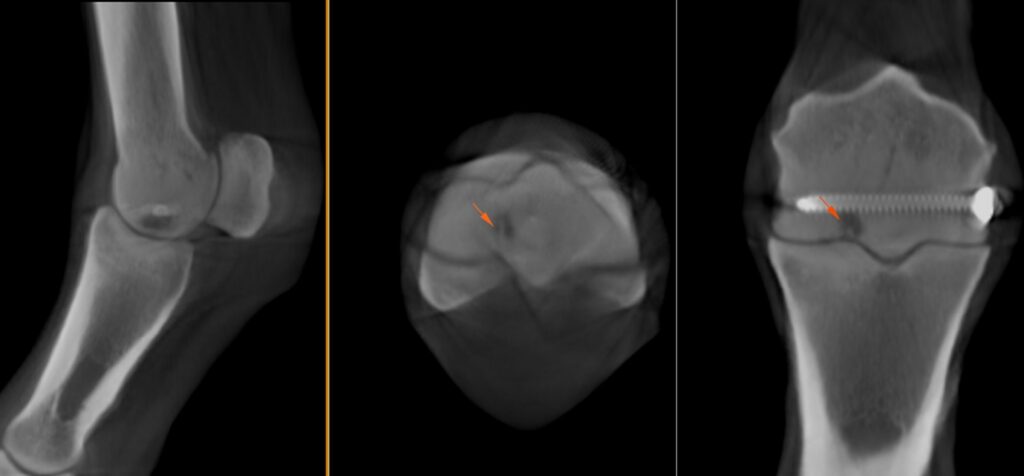

The area of osteolysis at the parasagittal groove of the medial condyle was well visualised, showing direct communication with the fetlock joint though two tracts (Figure 3). Additionally, the CT revealed a hypoattenuating line visible on all planes within the distal diaphysis of the third metacarpus extending from the region of the medial parasagittal groove spiralling medially, likely indicating a hair line fracture (Figure 4).